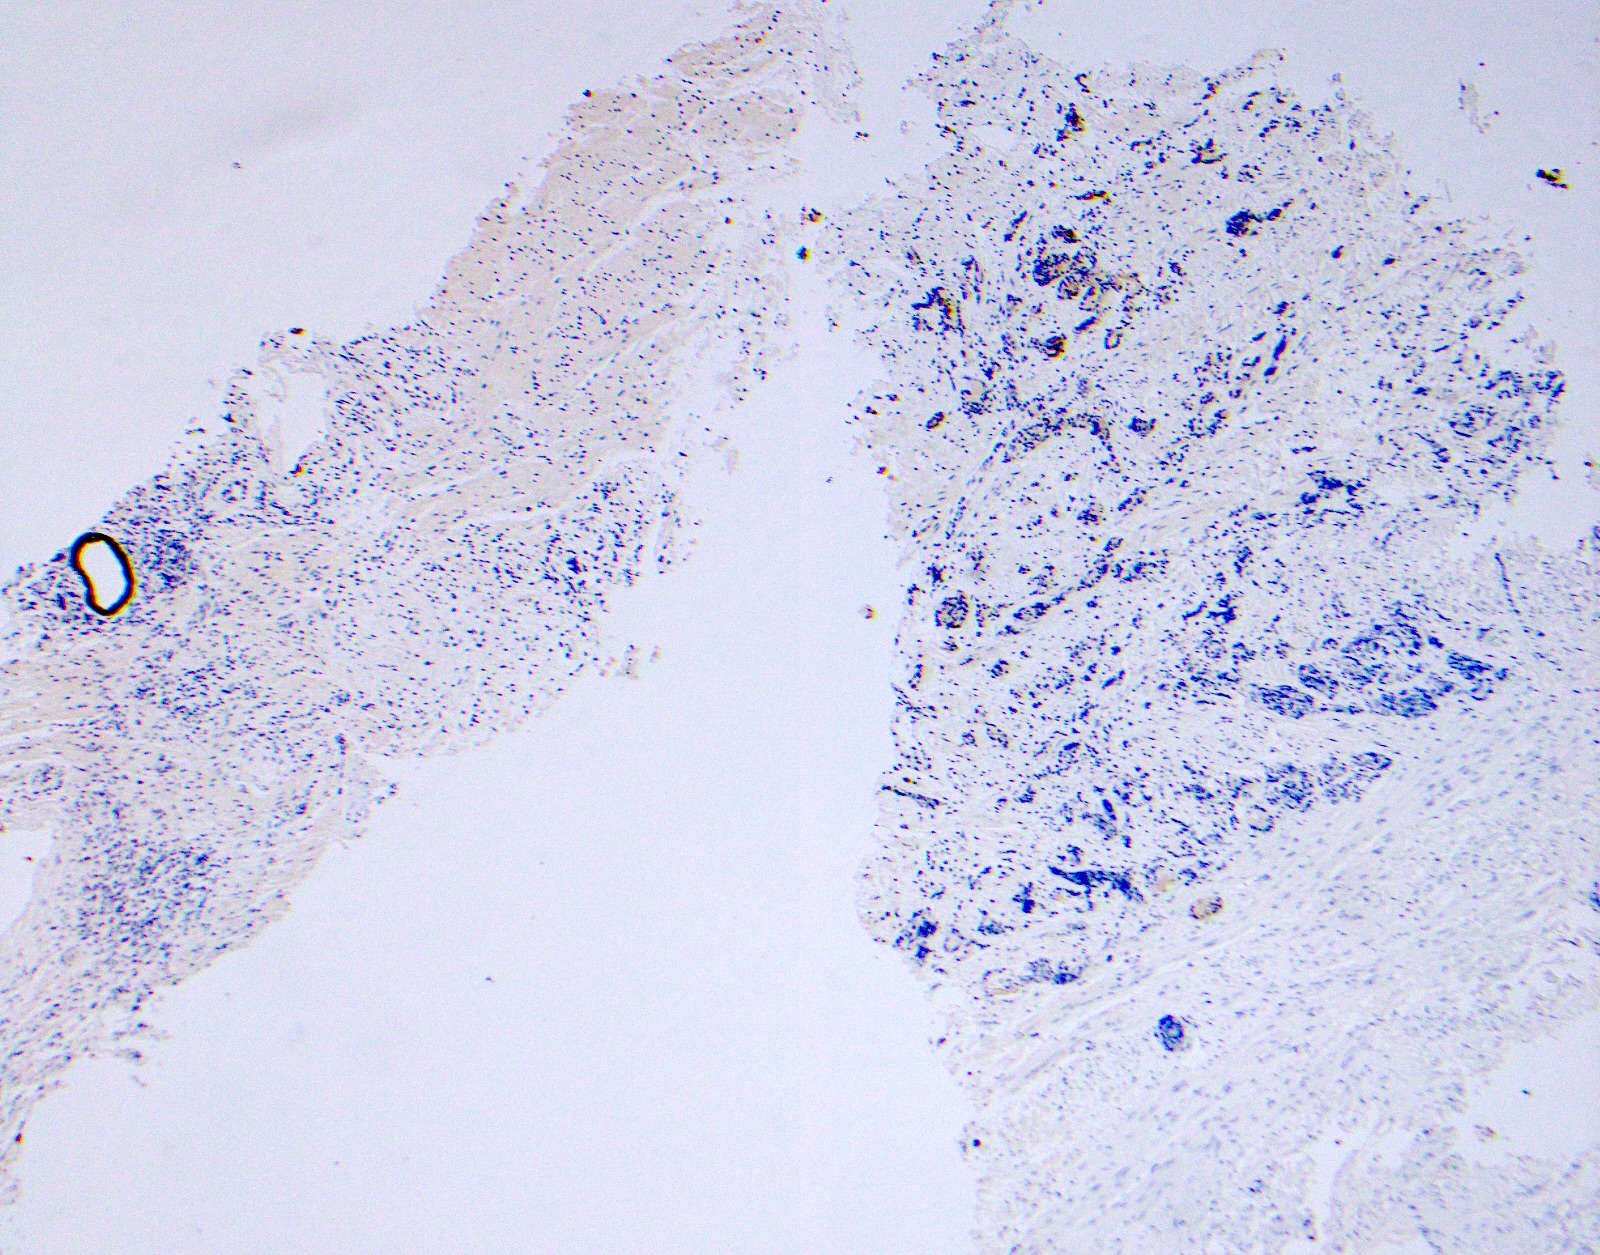

Microscopic (histologic) images

Contributed by Surekha Bantumilli, M.D. and Dimitri G. Trembath, M.D., Ph.D.

Negative staining

- Prostatic adenocarcinoma, usual type

- Benign mimickers of prostate carcinoma, including atrophy (23%), atypical adenomatous hyperplasia (AAH) (50%), nephrogenic adenoma (75%) and mesonephric hyperplasia (66%) (Ann Diagn Pathol 2013;17:41, Semin Diagn Pathol 2005;22:88)

Practice question #1

A 65 year old man presents with elevated prostate specific antigen (PSA) and undergoes a prostate biopsy, stained with high molecular weight cytokeratin (HMWCK) (shown above). What is the most likely interpretation of this staining pattern?

- Benign prostate tissue

- Benign seminal vesicle

- High grade prostatic intraepithelial neoplasia

- Prostatic adenocarcinoma

- Urothelial carcinoma

Practice answer #1

A. Benign prostate tissue. The basal layer of benign prostate glands will stain with high molecular weight cytokeratin. Answer D is incorrect because staining will be lost on prostatic adenocarcinoma. Answer C is incorrect because high molecular weight cytokeratin staining can be present in high grade prostatic intraepithelial neoplasia but is not diagnostic by itself for this entity. Answers B and E are incorrect because the glandular appearance outlined by the high molecular weight cytokeratin staining is not consistent with either seminal vesicle or urothelial carcinoma.